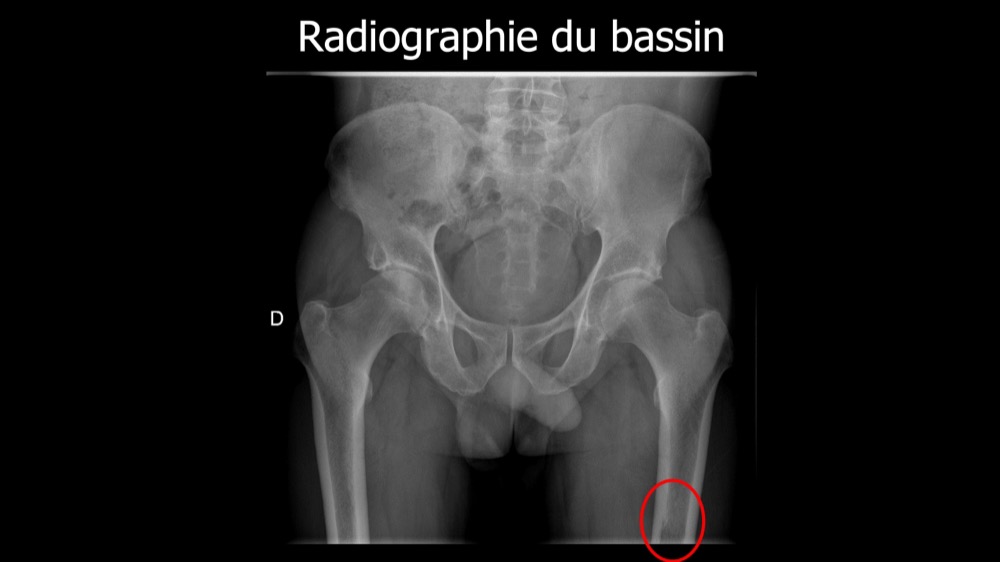

Lombo-cruralgie subaiguë trompeuse

Pascalie Jallerat 22/06/2020